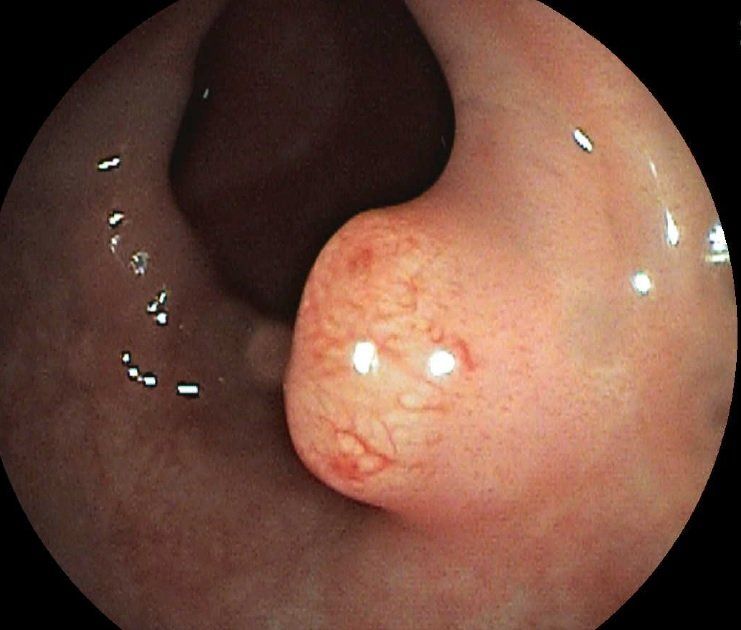

Dickdarmpolypen (Vorstufen von Darmkrebs)

Werden während der Untersuchung Auffälligkeiten festgestellt, müssen aus diesen Gebieten kleine Gewebeproben, die feingeweblich untersucht werden, entnommen werden - dies ist schmerzlos. Sollten sich Polypen zeigen, so können diese mit einer Drahtschlinge elektrisch abgeschnitten werden - auch dies ist schmerzlos. Die Darmspiegelung dauert etwa 30 Minuten. Nach der Untersuchung wird sofort ein Befund erstellt.